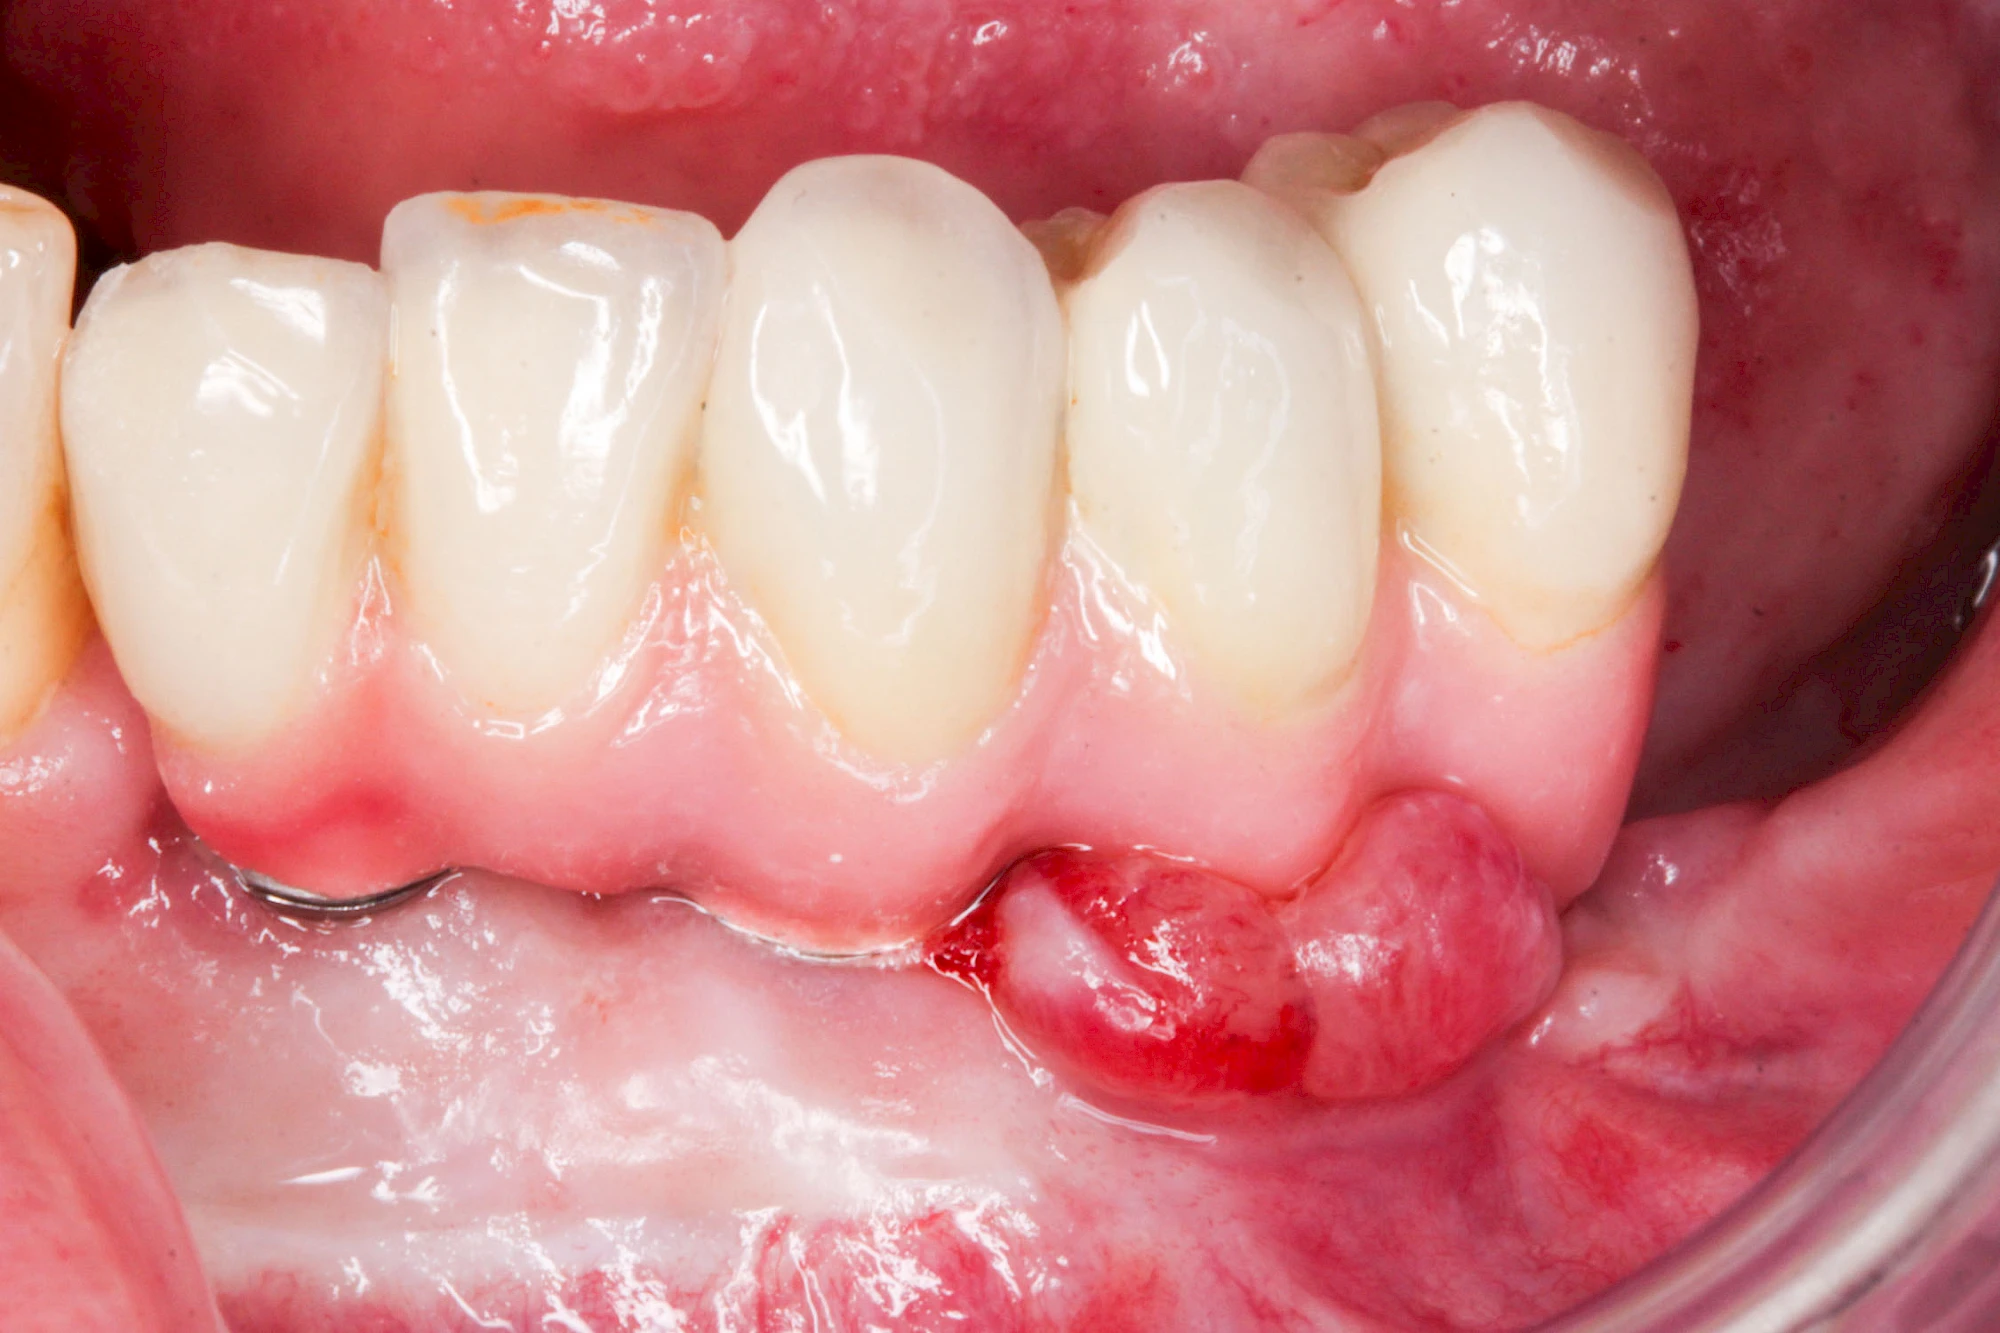

Sonderform: Wucherung

Epulis

Diese Vermehrung von Bindegewebe im Bereich des Zahnfleisches kann auf folgende Ursachen zurückgeführt werden:

- Hormonschwankung im Rahmen der Schwangerschaft (Schwangerschaftsepulis)

Diese Vermehrung von Bindegewebe in einem frei gewordenen Raum ist eine Sonderform der Anpassungsreaktion menschlicher Zellen und wird als Vakatwucherung bezeichnet.

Früher wurden im Unterkiefer mitunter Brücken zum Ersatz fehlender Zähne als sogenannte "Schwebebrücken" gestaltet. Die Idee dabei war, dass man die Brücke insgesamt besser reinigen kann. Allerdings war das für die Patienten mitunter irritierend für die Zunge und vor allem beim Essen gewöhnungsbedürftig. Teilweise haben sich hier reaktiv Vakatwucherungen der Kieferkammschleimhaut gebildet und den Raum unter der Brücke wieder verschlossen.